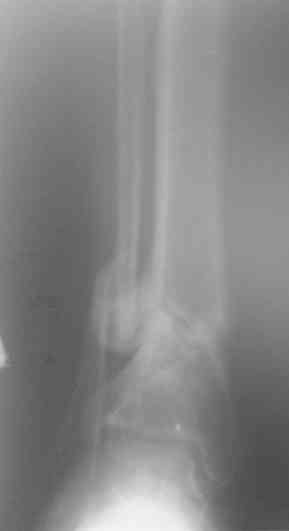

У меня сейчас лечится похожий пациент - ему стрельнули в упор из охотничьего ружья: открытый скозной перелом правой голени в н/3 с дефектом костной ткани до 6 см. При поступлении наложили ап.Илизарова. После отторжения всех некрозов и несмотря на сохраняющиеся раны (чтобы не терять время) мы провели повторную операцию - наростили аппарат Илизарова вверх на одно кольцо, под которым сделали поперечную остеотомию большеберцовой кости (в проксимальном метафизе) и теперь низводим образовавшийся промежуточный фрагмент по 1-2 мм в сутки при сохранении общей длины конечности. В месте остеотомии растет регенерат, который постоянно рентген-контролируем. Думаю что это самый лучший вариант для подобного рода травм. Если будет интересно могу показать снимки (как раз скоро очередной рентген-контроль).

Есть у меня результат такого метода. Тема обсуждалась. Как говорится - лечили всем форумом. Рана, правда, не огнестрельная - OFFтопик.

Больной случайно попал в поле зрения с переломом шейки бедра. Страдает хр. алкоголизмом. От когда-то предложенного удлиннения голени пациент отказался. После снятия аппарата он пропал как с белых яблонь дым ...

Укорочение конечности 3 см. Передвигался без дополнительной опоры с "нарощенной" подошвой на правой обуви. Ограничение тыльного и подошвенного сгибания - умеренные (всего примерно 50%, не измерял).